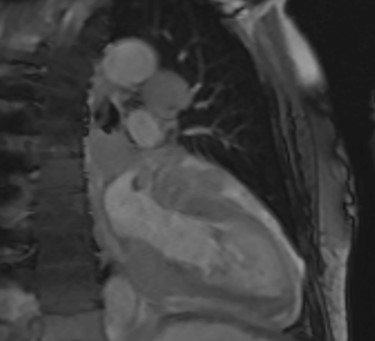

Intraoperatively, he developed new t-wave inversion on lead II of the 3-lead electrocardiogram (ECG). This resolved post-operatively, and he denied chest pain. He was kept in overnight for observation. The next morning, during the round, he reported central crushing chest pain the previous day that he had not disclosed. His ECG was repeated and demonstrated the t-wave inversion in lead II—indicating dynamic ECG changes. A troponin I level measured 27. As such, management for a non-ST elevation myocardial infarction was initiated and a cardiology consult organized, who advised continued acute coronary syndrome (ACS) treatment and an echocardiogram. This demonstrated a ‘pericardial mass (subcostal 3 cm × 2.5 cm) encroaching and extending outwards on both sides of the right atrioventricular groove’. ACS protocol was stopped and a cardiac magnetic resonance imaging (MRI) was organized (Figs 2 and 3).

Cardiac MRI (transverse plane) demonstrating an enhancing lesion surrounding the chambers of the heart.

This demonstrated a bulky mediastinal tissue (measuring 50% of the heart) that encased all the aorta and pulmonary artery as well as the coronary artery. It has malignant behaviour with multiple foci that breached fascial planes. It restricted the long axis of the heart but was not causing haemodynamic occlusion. It was non-resectable.